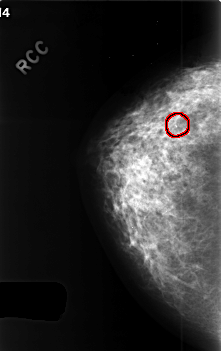

C_0413_1.RIGHT_CC

FILE: C_0413_1.RIGHT_CC.OVERLAY

TOTAL_ABNORMALITIES 1

ABNORMALITY 1

LESION_TYPE CALCIFICATION TYPE AMORPHOUS DISTRIBUTION CLUSTERED

ASSESSMENT 4

SUBTLETY 4

PATHOLOGY BENIGN

TOTAL_OUTLINES 1

BOUNDARY